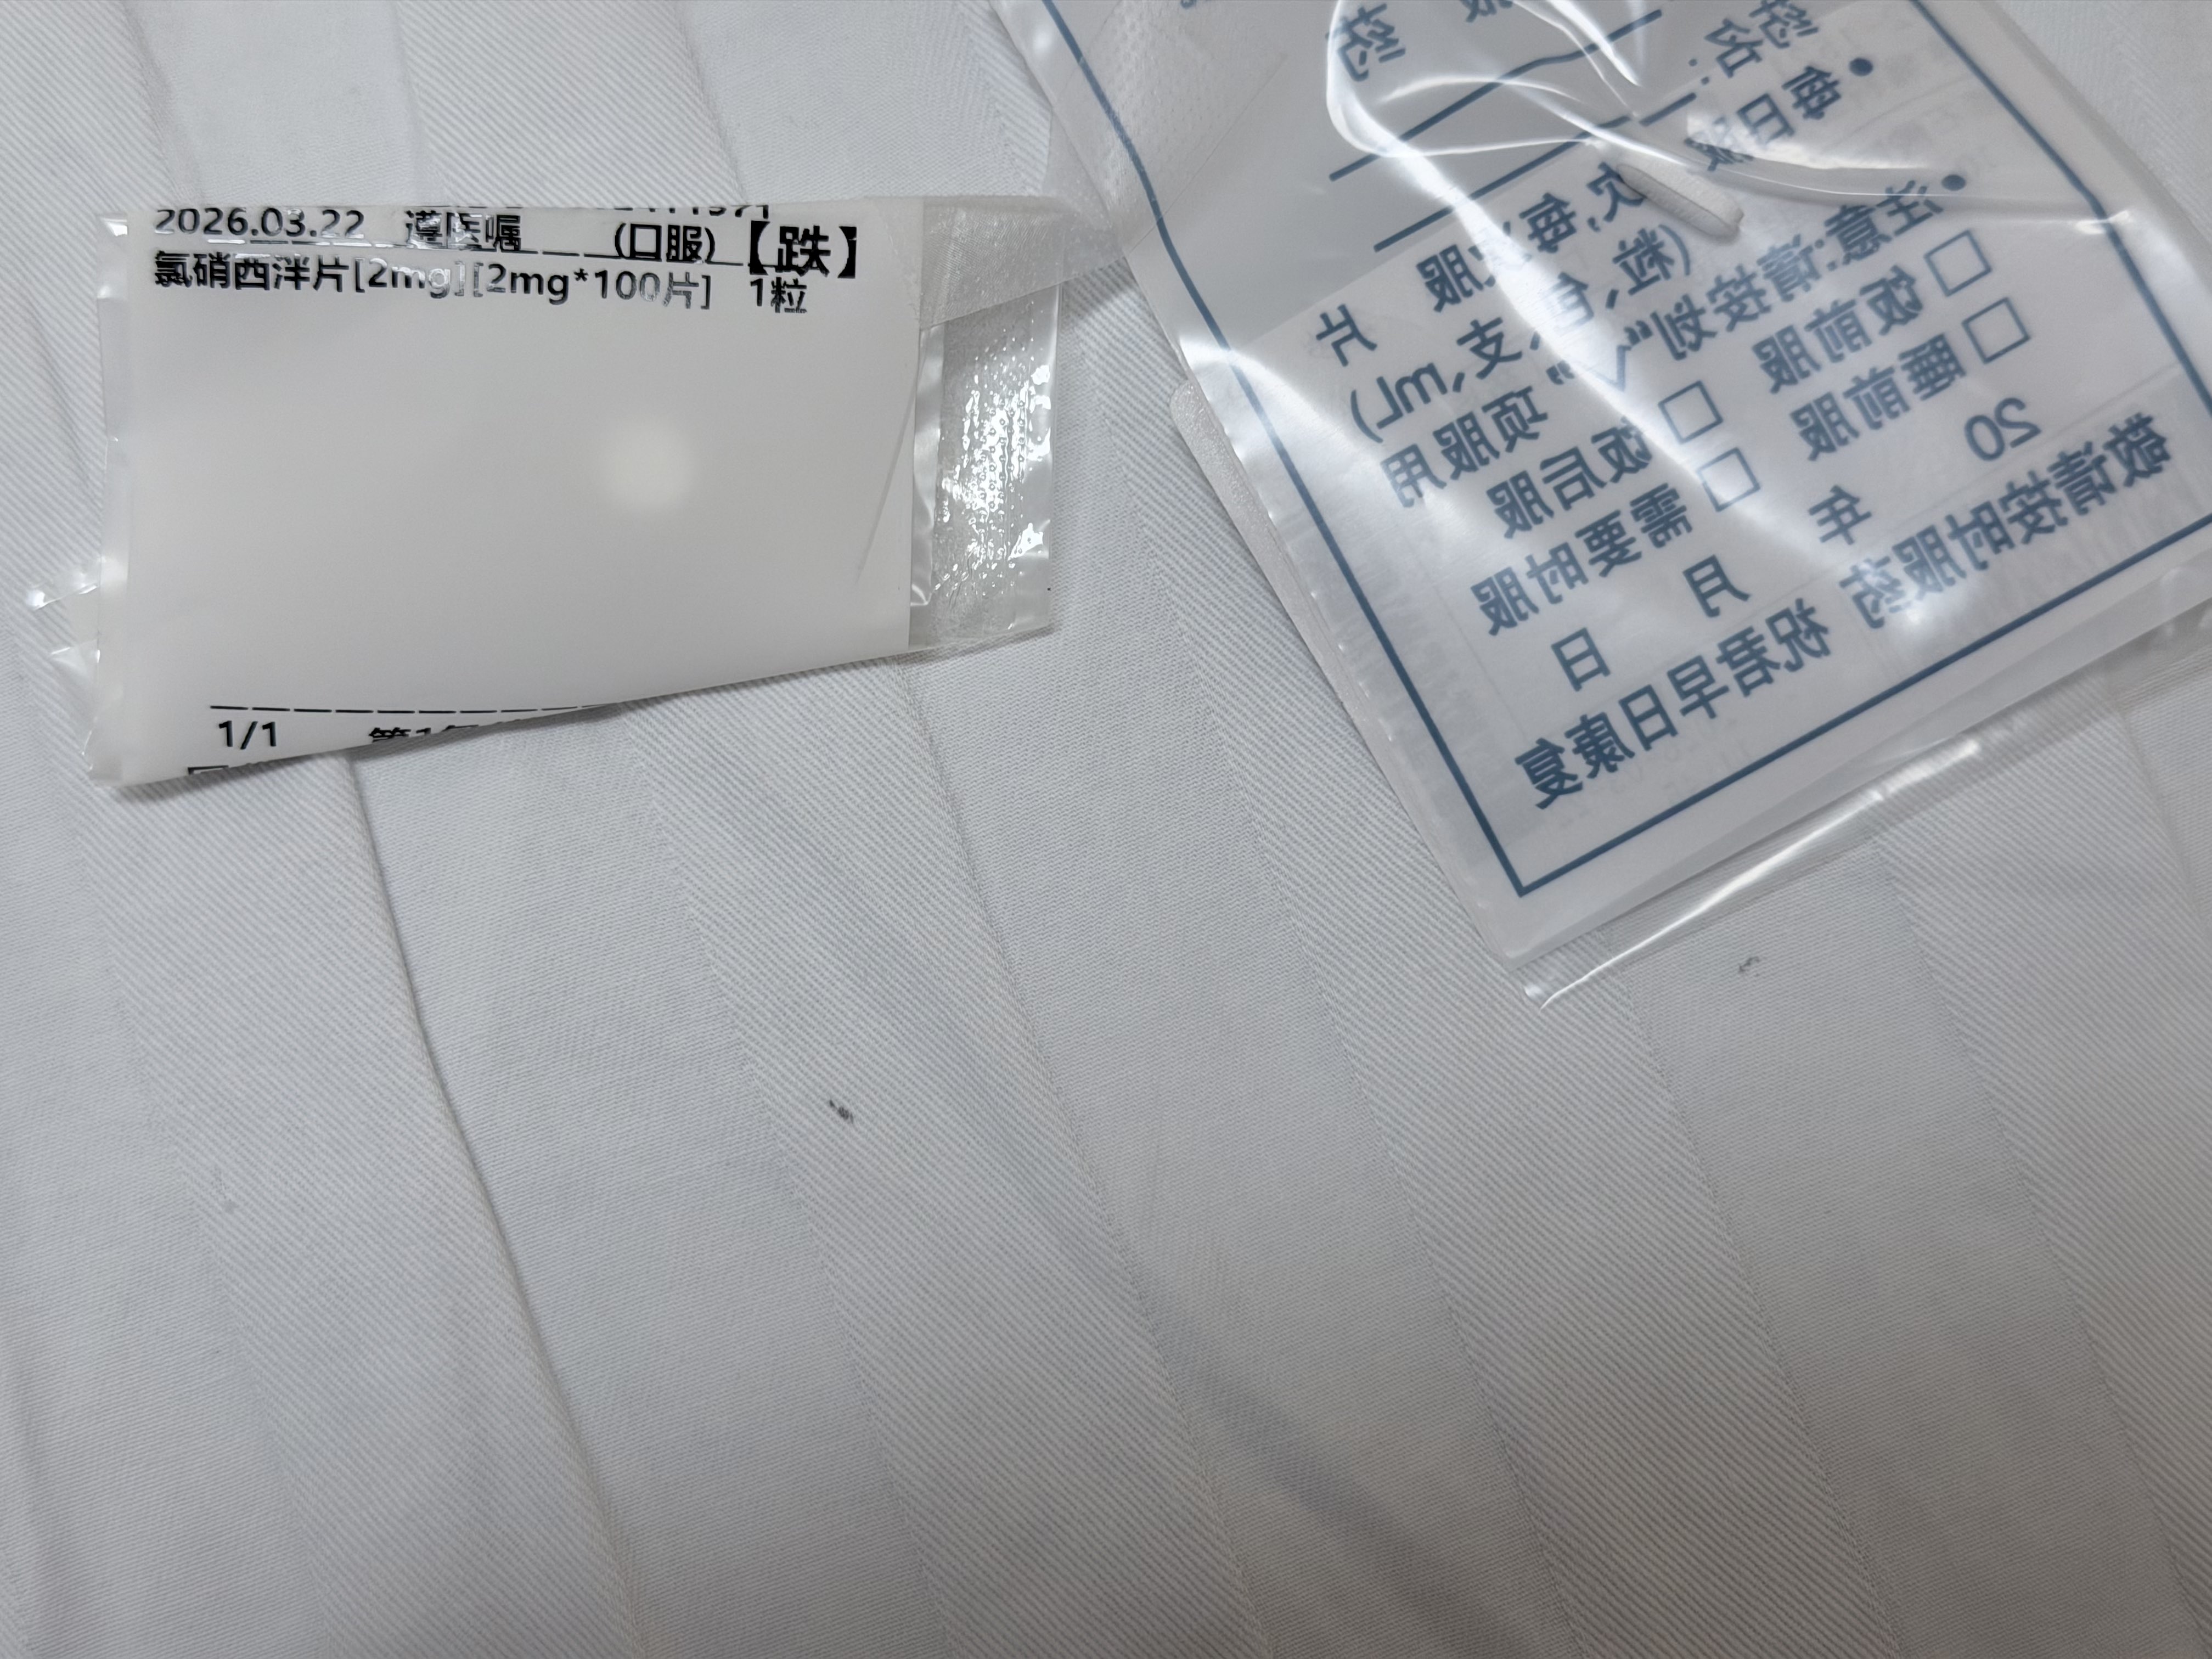

半片氯硝让幽灵退回了阴影中